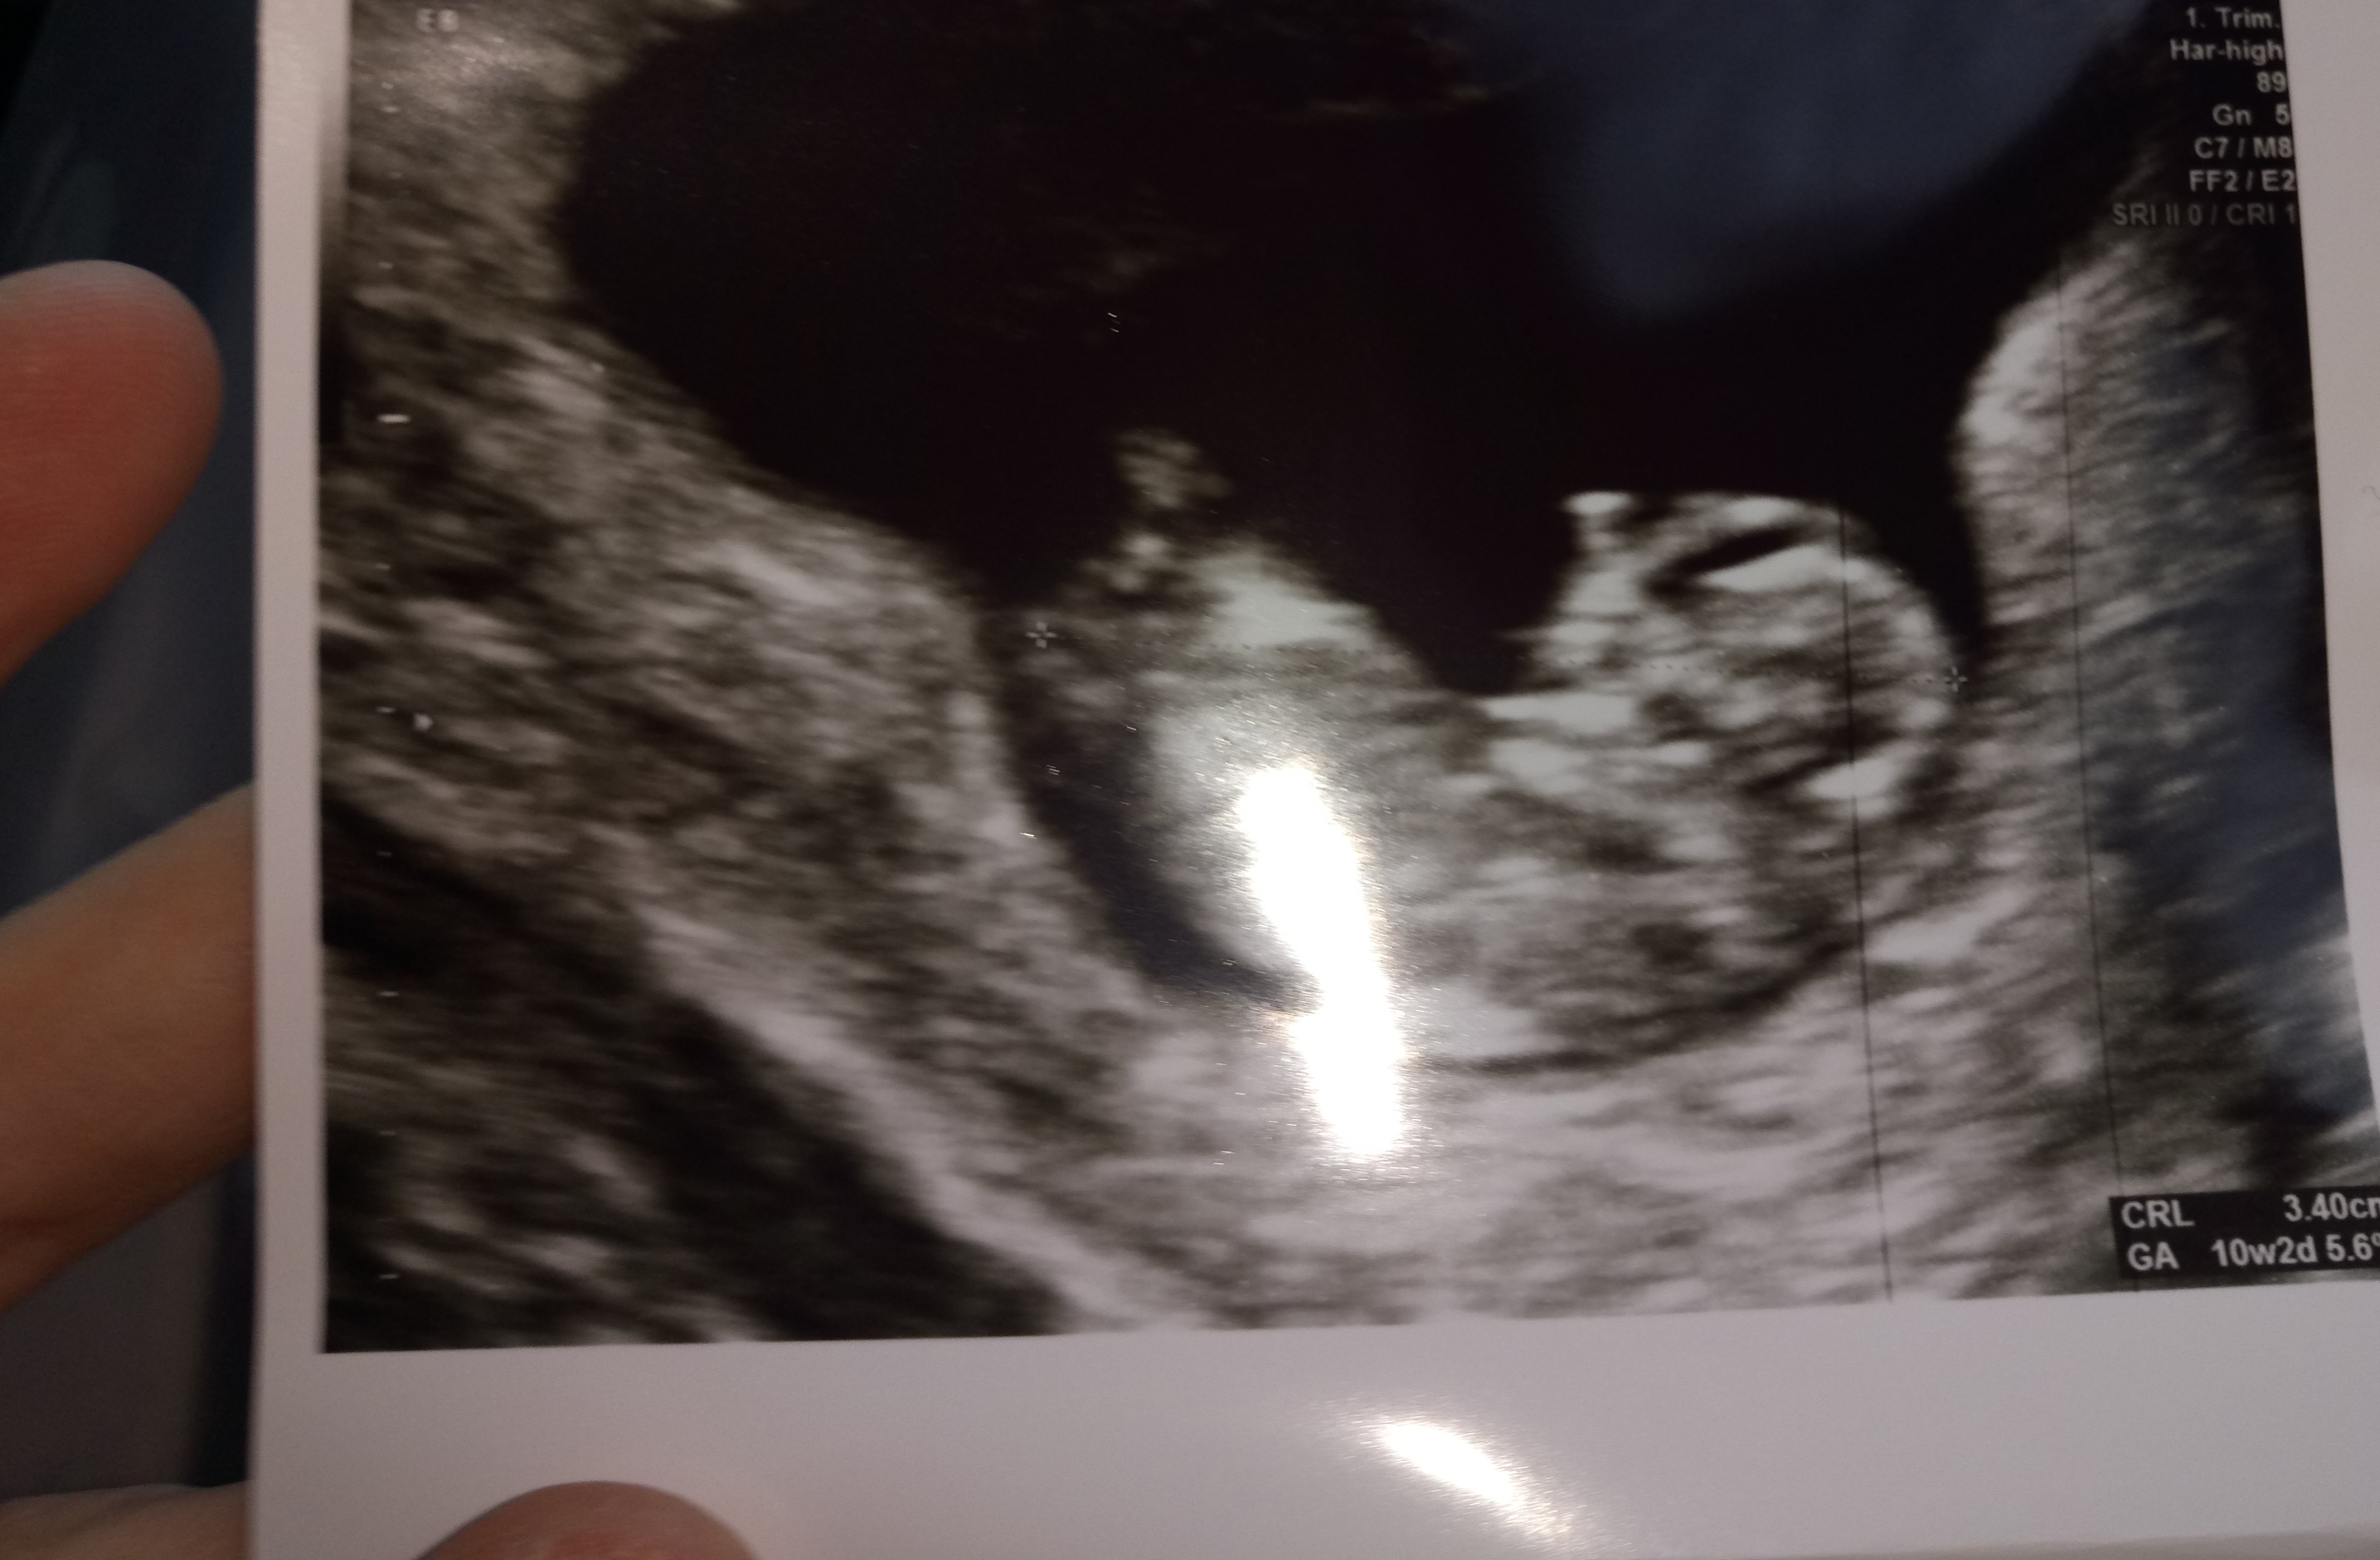

Jestem po wizycie! :) dzidzia tak fajnie skakala że mój mąż aż pytał czy on na prawdę tak skacze? Hehe dziwił a ja się śmiałam że aż obraz znikał z dzidzia tak mnie śmieszyl ehhe i ręce i nogi i nawet paluszki u stopek widzieliśmy tak pan doktor mówił hehe no i co najlepsze machal tak nogami że widać było co niego miedzy nogami że lekarz mówi że wygląda mu na chlopaka że jeszcze za wcześnie ale mówi że tak widać mocno że aż zaznaczył w karcie chłopak że znakiem zapytania hehe

Limonka gratuluję, super wieści po wizycie! Super, że już co nieco wiecie o płci. Ja się już nie mogę doczekać tej informacji.

Przecudny człowieczek [emoji7]